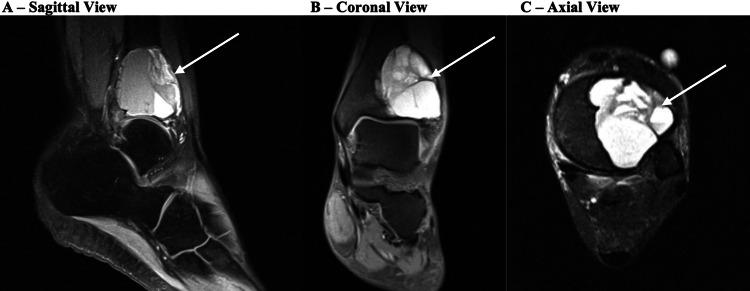

Reconstruction options for giant cell tumors (GCTs) of bone are limited and challenging due to the amount of structural compromise and the high recurrence rates. This is especially true for GCTs of the foot and ankle, as the area is vital for weight bearing and function. The typical treatment for GCTs is currently excision, curettage, and cementation, although that is not always effective. A 36-year-old otherwise healthy female presented with an original diagnosis of a large aneurysmal bone cyst (ABC) of the distal tibia that had recurred despite two previous attempts at treatment with resection and cementation. She was treated with surgical resection of the lesion, reconstruction, and ankle and subtalar joint arthrodesis with a tibiotalocalcaneal intramedullary nail in combination with a trabecular metal cone. The final pathology of the intraoperative samples was consistent with GCT. Postoperatively, she recovered well, and her imaging was consistent with a successful fusion. This case report provides evidence that tibiotalocalcaneal fusion with a unique combination of hindfoot nail and trabecular metal cone construct in a single procedure is a successful option for the treatment of large, recurrent GCT lesions in the distal tibia.

由于骨巨细胞瘤(GCT)造成的结构破坏程度以及高复发率,其重建选择有限且具有挑战性。对于足踝部的GCT尤其如此,因为该区域对负重和功能至关重要。目前GCT的典型治疗方法是切除、刮除和骨水泥填充,尽管并非总是有效。一名36岁的健康女性最初被诊断为胫骨远端的巨大骨囊肿(ABC),尽管此前曾两次尝试切除并骨水泥填充治疗,但仍复发。她接受了病变的手术切除、重建,以及使用胫距跟髓内钉联合小梁金属锥进行踝关节和距下关节融合术。术中样本的最终病理结果与GCT一致。术后,她恢复良好,影像学检查显示融合成功。本病例报告证明,在单一手术中使用独特的后足钉和小梁金属锥结构进行胫距跟融合术是治疗胫骨远端大型复发性GCT病变的成功选择。